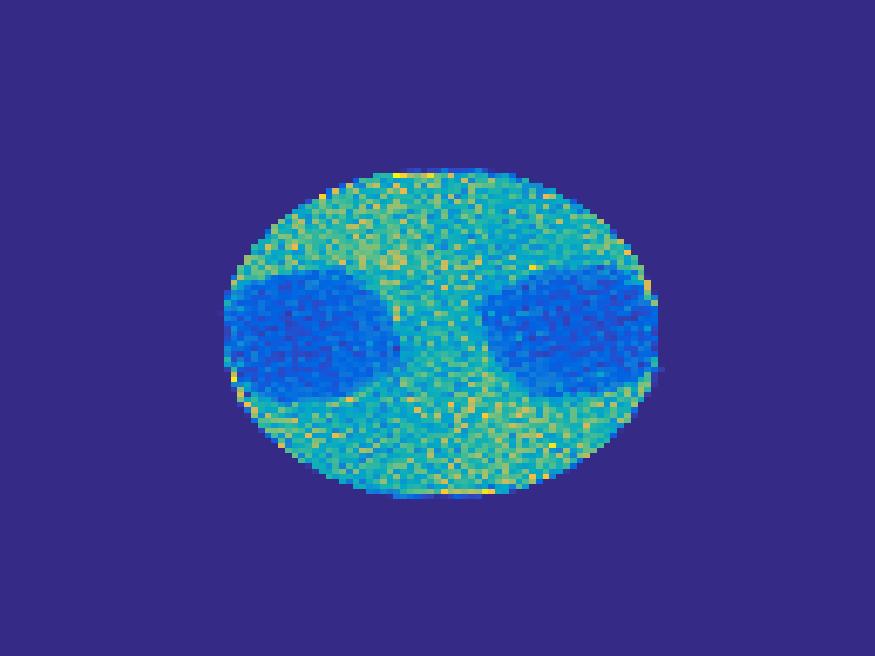

The proposed method is tested on numerical phantoms for a proof of concept study. We simulate image frames of size and projections per frame. Three time activity curves (TAC) for blood, liver and myocardium, previously used in [14] (see Figure 1), are used to simulate the dynamic images. The first simulated dynamic phantom is composed of two ellipses. In temporal direction, the positions of the two ellipses are stationary while the intensity in 90 frames within the region of each ellipse is generated according to the TAC of blood or liver. The projections are generated by using Radon transform sequentially performed for each frame.

In the tests, projections at two orthogonal angles are simulated for every frame to mimic 2-head camera data collection. The projection angles increase sequentially by along temporal direction. For example, at frame 1, projections are simulated at angle and , and at frame 2, angle and , etc. Finally, white Gaussian noise is added to the projection data. Reconstruction results with different methods are shown in Figure 3. Since the number of projections is very limited for each frame, the traditional FBP and least square methods cannot reconstruct the images satisfactorily, while the proposed method is capable to reconstruct the images effectively. Compared with SEMF model, when the edge of images jump (see frame 21 -frame 31 in Figure 3), the proposed model can better capture the change of the tendency of TAC.